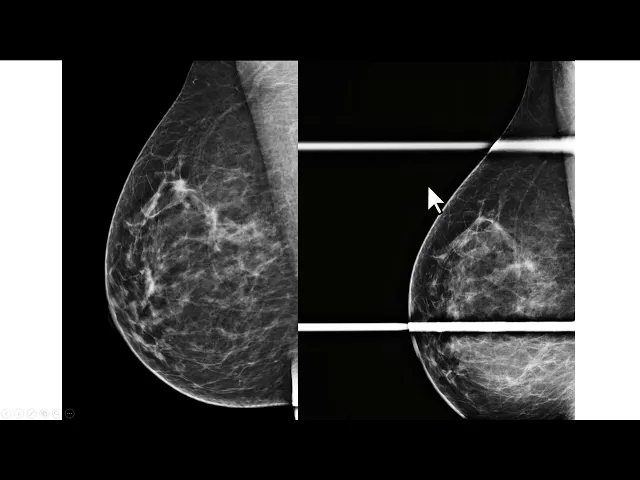

Olá eu sou professor Rodrigo Jales do serviço de imagem do Hospital da Mulher da Unicamp hoje eu quero mostrar para vocês é essa mamografia trata-se de uma paciente com cerca de 60 anos com antecedência de ter tratado um câncer na mama esquerda com cirurgia conservadora veja que algumas alterações cicatriciais algumas distinção arquitetural nos quadrantes superiores no prolongamento axilar algumas classificações de estrofes aqui embaixo talvez algum espessamento cutâneo quando comparado com a mão uma contra lateral ou seja achados frequentes no tratamento conservador dama Mas o que eu quero mostrar para vocês é esse nódulo incidência médio

lateral-bico à direita irregular e permanência talvez especulado que seria um nódulo suspeito desde que aparecesse na incidência crê no caudal veja então que na outra incidência de rastreamento não há nenhuma imagem semelhante aquele nódulo essa situação em que a morfologia de um nó identificada em apenas uma das duas incidências de rastreamento é definida como assimetria na maioria das vezes a comparação com os exames anteriores é suficiente para segurar a benignidade do achado essa aqui é incidência médio lateral glico anterior da paciente realizado cerca de um ano antes dessa mamografia que eu mostrei para vocês veja

que nesses tema anterior a paciente tinha mais parei com a fibrilandular nos quadrantes superiores mas essa simetria que nos chamam atenção aqui na extremidade superior do Paraíso glandular não estava presente dessa forma precisamos realizar uma incidência monográfica complementar para nos certificar que esse achado e não tem importância Clínica a recomendação nesses casos é a compressão focal preferencialmente realizada na incidência em perfil veja que no perfil aparece menos um músculo peitoral maior do que aparece na incidência né de lateral oblíqua a compressão no perfil ajuda de associar a disposição do parenque os nódulos reais se Mantena

com pressão no perfil enquanto a sobreposição do parênquima é resolvida Principalmente quando a incidência do perfil é complementada com a compressão localizada veja que a maior parte da força do compressor foi aplicada na região de interesse passa a ser melhor avaliada depois da incidência complementar nós podemos interpretar esse achado como irrelevante ele pode ser descrito como uma sobreposição de parenquima justificando uma simetria nesse caso classificado na categoria B2 ou então nem precisa ser descrito mas o exame continuarei sendo classificada na categoria devido aos achados cicatriciais não é contra lateral se você ainda não está inscrito